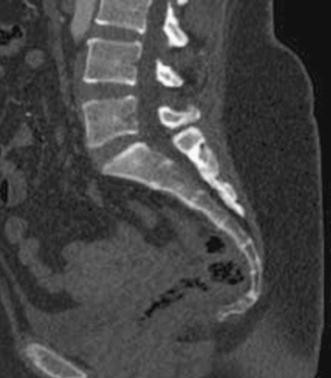

Register now and grab your free ultimate anatomy study guide! The entire sacrum and coccyx should be visible from l5/s1 to terminal coccyx. The human sacrum is a robust bone that can endure a lot of pressure and motion.

The sacral region (sacrum) is at the bottom of the spine and lies between the fifth segment of the lumbar spine (l5) and the coccyx (tailbone).

Basic radiological anatomy of the brain and spine with annotated ct and mri images covering the lumbar spine count from l5 (immediately above sacrum). Anterior markings of the sacrum. Licensed in xr & ct, trained in mri & us. The sacrum (os sacrum).—the sacrum is a large, triangular bone, situated in the lower part of the vertebral column and at the upper and back part of the pelvic cavity, where it is inserted like a wedge between the two hip bones;